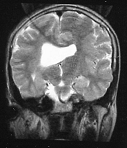

Mapeamento cerebral com EEG para estudo do aprendizado da leitura

Diagnóstico